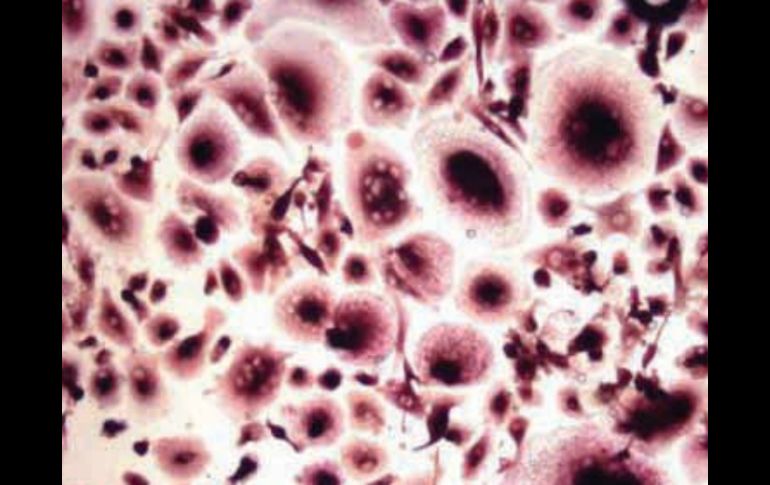

Tecnología | Las mujeres tienen un factor extra que vuelve más difícil el tratamiento Estrógenos favorecen desarrollo de cáncer pulmonar Favorecen la producción de quimiocinas implicados en el desarrollo del cáncer pulmonar en mujeres Por: SUN 18 de agosto de 2011 - 12:32 hs Aún se conoce poco del mecanismo mediante el que las hormonas sexuales femeninas participan en el proceso. ESPECIAL / CIUDAD DE MÉXICO (18/AGO/2011).- Los estrógenos, hormonas sexuales femeninas, favorecen la producción de quimiocinas implicados en el desarrollo del cáncer pulmonar en mujeres. Ello significa que las mujeres tienen un factor extra que vuelve más difícil el tratamiento y la respuesta, subrayó Vianey Rodríguez Lara, maestra en Ciencias, quien realiza un proyecto de investigación en el Departamento de Biología Celular y Tisular de la Facultad de Medicina de la UNAM. Las quimiocinas son moléculas que normalmente ayudan a las células del sistema inmune a migrar a sitios donde hay una infección, para que puedan llevar a cabo su "trabajo de limpieza". Sin embargo, si las pertenecientes a un tumor expresan esas moléculas las utilizan para trasladarse a donde hay más quimiocinas. De esta manera, es favorecida la metástasis. Aún se conoce poco del mecanismo mediante el que las hormonas sexuales femeninas participan en el proceso. "No se ha reportado que los estrógenos por sí solos ocasionen ese tipo de neoplasia; constituyen un factor de riesgo importante, pero se requieren otros elementos, como algunas alteraciones genéticas", dijo Rodríguez Lara, quien busca obtener su doctorado en Ciencias Biológicas con este trabajo. Teresa Fortoul, quien asesora la investigación, explicó que el ambiente donde se desarrolla un cáncer puede ser modulado por los estrógenos, y aquí entran en juego las quimiocinas, moléculas que modifican el "nido" donde las células enfermas pueden crecer. "Es fundamental conocer de qué modo participan los estrógenos, para saber si es necesario inhibirlos como parte del tratamiento contra ese padecimiento y, también, para ver si la terapia de reemplazo hormonal podría favorecer el curso del proceso neoplásico en los pulmones", indicó Rodríguez. Hasta ahora, las investigadoras han encontrado que las hormonas femeninas favorecen la expresión de las quimiocinas en el microambiente del tumor, lo que facilita que las células neoplásicas proliferen, migren a otros sitios y hagan metástasis. "Actualmente hombres y mujeres reciben el mismo tratamiento, pero en el futuro se buscaría planear uno diferente para ellas", dijo Fortoul. Temas Cáncer Ciencia médica Enfermedades Lee También Octubre Rosa: ¿Cuánto cuesta una mastografía en Jalisco según Profeco? Nobel de Química premia el desarrollo de estructuras metal-orgánicas Nobel de Física para Clarke, Devoret y Martinis por descubrimiento sobre fenómenos cuánticos ¿Cuáles son los signos y síntomas del cáncer de mama? Recibe las últimas noticias en tu e-mail Todo lo que necesitas saber para comenzar tu día Registrarse implica aceptar los Términos y Condiciones